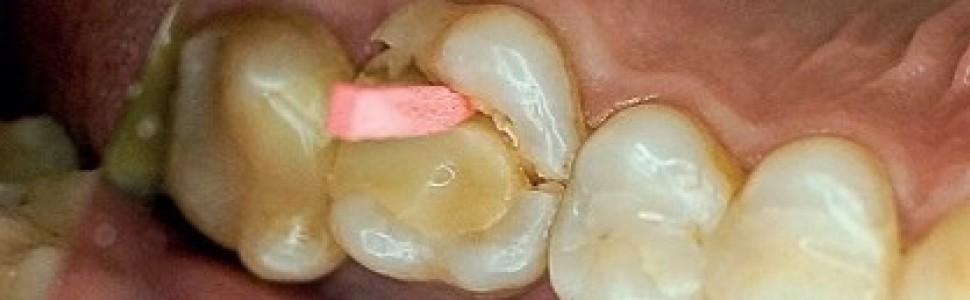

Zęby leczone endodontycznie są obciążone większym ryzykiem złamania, które może mieć ponadto katastrofalny przebieg (ryc. 4).

Ryc. 4. Katastrofalne złamanie korony zęba leczonego endodontycznie z rozległym wypełnieniem kompozytowym.